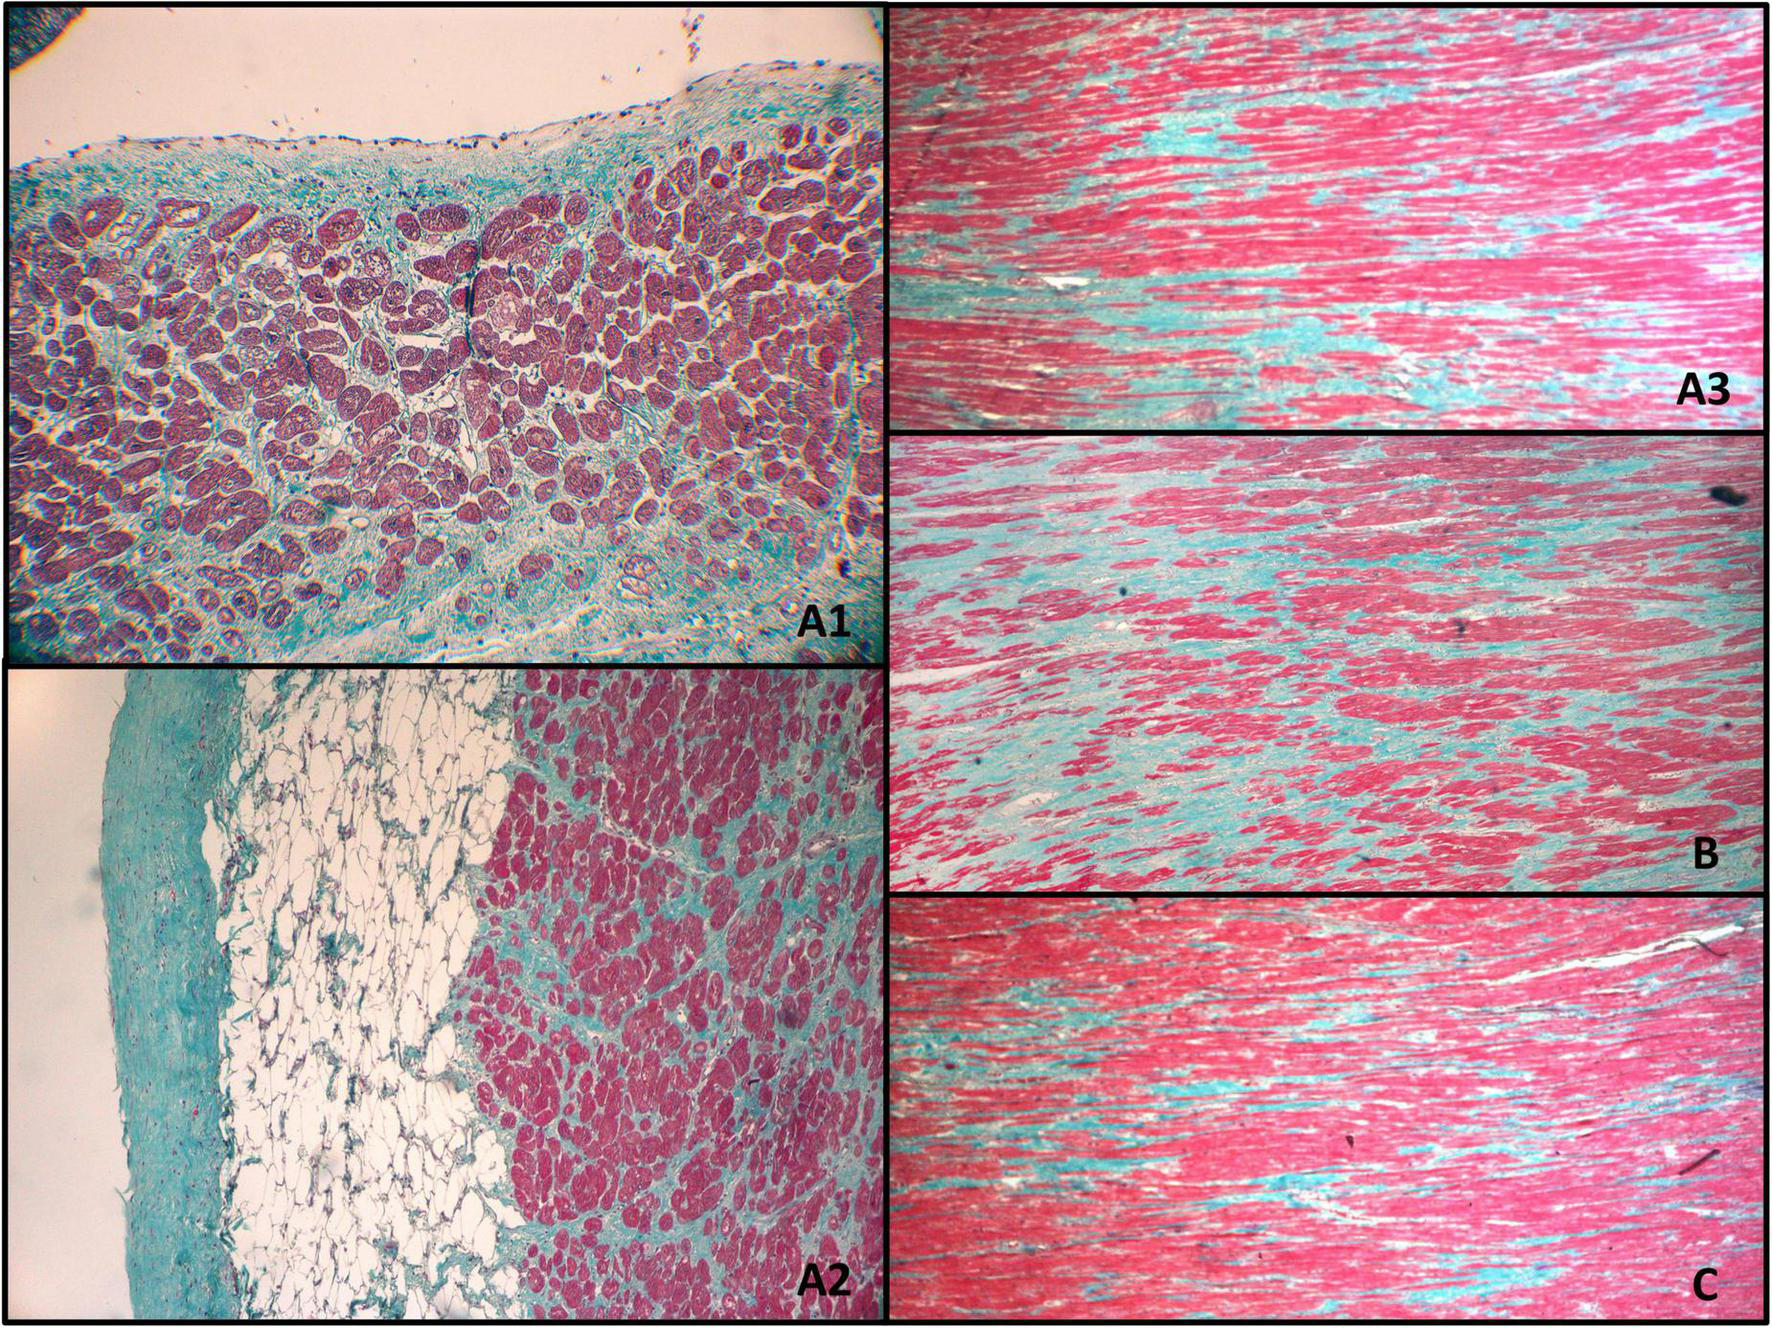

The myocardium within the irradiated region (Figures 6A1–A3,B) presented with multifocal, mosaic-like fibrosis, and neovascularization of intramuscular connective tissue scars. There were no visible signs of active inflammatory infiltration. The non-homogenous fibrosis was slightly more pronounced sub-endocardial, but there was no transmural scar. The pathological features of the irradiated myocardium were significantly different from the expected sequelae observed after RFA.

FIGURE 6

Myocardium 12 months after transmural irradiation with a single dose of 25 Gy. The letters indicate the localization of the specimens as shown in Figure 4. Figures (A1–A3,B) were located within the PTV and received approximately 25 Gy, while (C) was taken from a non-irradiated region. (A1) Endocardium; (A2) epicardium; (A3) middle part of the myocardium; (B) middle part of the myocardium; (C) middle part of the myocardium (non-irradiated region).

Considering that the irradiation was performed in the previously ischemic part of the myocardium, the fibrosis could have been associated with pre-existing ischemic damage to the heart. Moreover, a different etiology of the fibrosis is also suggested by the fact that some of the non-irradiated or marginally irradiated regions presented a similar pattern of fibrosis, albeit subjectively less intense, compared to fully irradiated regions (Figure 6C).

Compared to other explanted hearts, the pathological image of the specimen closely resembled those of ischemic cardiomyopathy, and it would not be feasible to determine that this patient had undergone STAR based on pathology examination alone. There was no aneurysm, transmural fibrosis, or resorption of necrosis. The post-STAR region was significantly different from the pre-existing post-RFA scar.